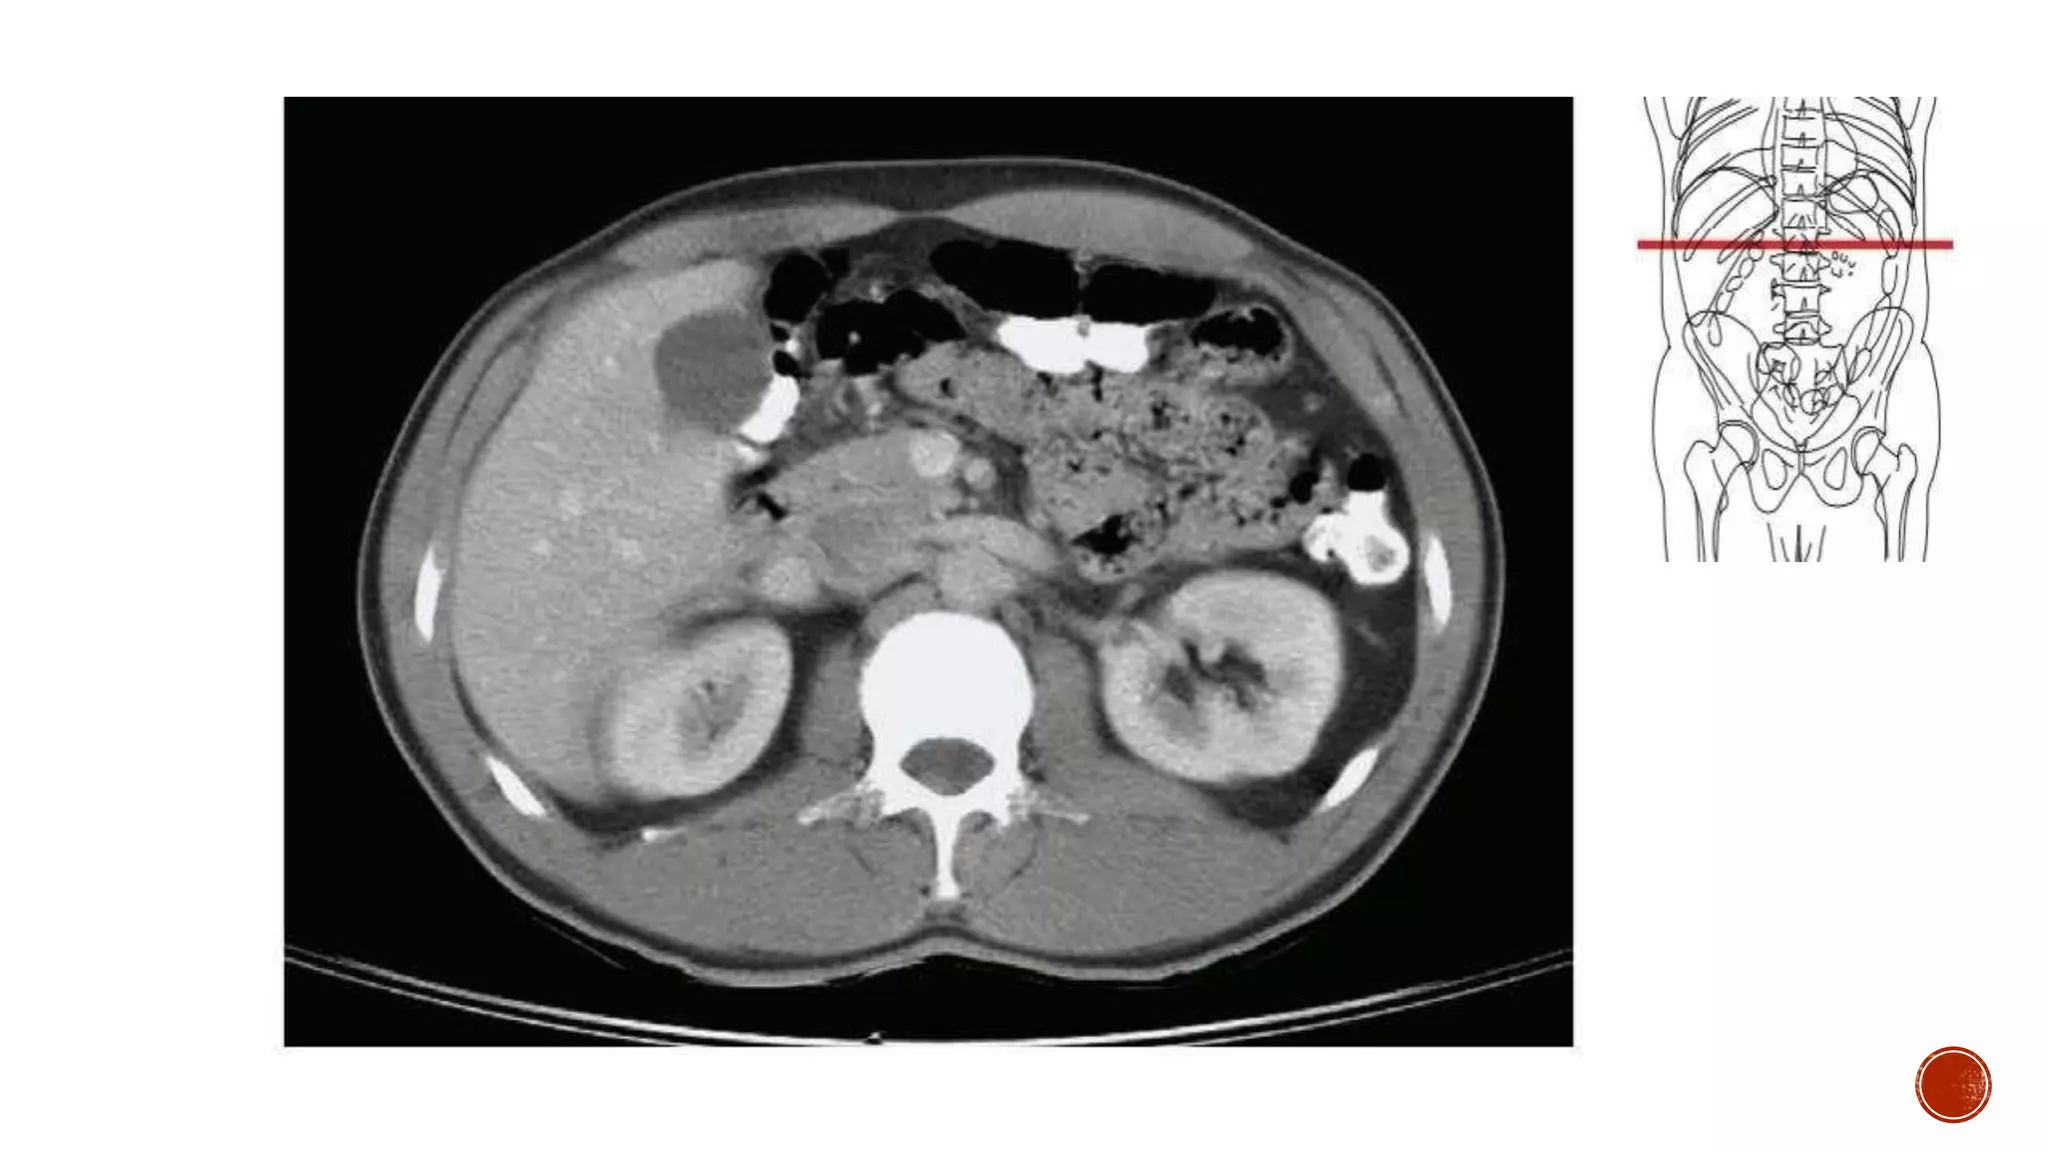

The document describes the anatomy of the abdomen and pelvis region of the human body. It lists over 40 structures and their locations, including major organs like the liver, kidneys, intestines, blood vessels and muscles of the abdominal wall and pelvis. The structures are grouped into sections focusing on different anatomical areas like the abdomen, retroperitoneum, pelvis and gluteal region.